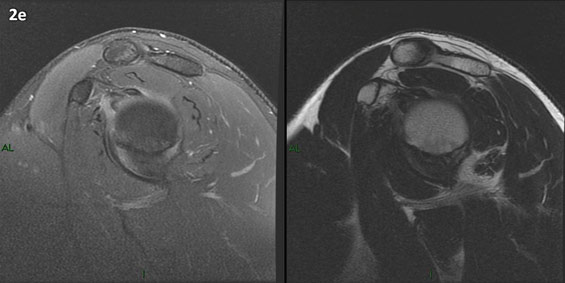

Figura 2 (a-j): Imagens consecutivas de RM no plano sagital nas ponderações T2 com supressão de gordura (DP SG) à esquerda e T2 à direita. Clique na seta para passar as imagens.

Figura 2 (a-j)': Imagens consecutivas de RM no plano sagital nas ponderaçõesT2 com supressão de gordura (DP SG) à esquerda e T2 à direita. Clique na seta para passar as imagens.

Figuras 2b a 2j’: Acompanhando o tendão do redondo menor (seta amarela fina) é possível notar lipossubstituição ao redor da junção miotendínea (setas amarelas grossas) e a atrofia principalmente da porção mais lateral (seta salmão). A porção mais medial (seta branca) tem volume preservado.

Repare que estas alterações também não são evidentes nas imagens com supressão de gordura no plano sagital.

Chafik et al. também relataram a presença de um pequeno nervo motor acessório em número variável que se insere na porção lateral do músculo redondo menor. O nervo acessório, ao contrário do principal, tem um curso reto e extra-fascial, sendo menos vulnerável aos efeitos compressivos. De fato, nos casos da atrofia parcial do redondo menor, é mais frequente a atrofia da porção mediodorsal com preservação da porção lateroventral, o que poderia ser explicada pela presença do ramo acessório mais lateral do nervo axilar, embora atrofia isolada do componente lateroventral tenha sido reportada em cerca de 17% dos casos de atrofia de apenas uma porção, o que pode ter sido causada por lesão do nervo acessório. No caso do paciente deste mês, a atrofia é mais evidente nesta porção mais lateral e ventral do redondo menor.

É importante que o protocolo de ressonância magnética do ombro tenha sequências ponderadas em T1, T2 ou densidade protônica (DP) sem supressão de gordura em pelo menos dois planos, idealmente nos planos coronal e sagital, para a detecção de lipossubstituição que pode passar despercebida nas imagens com supressão de gordura.